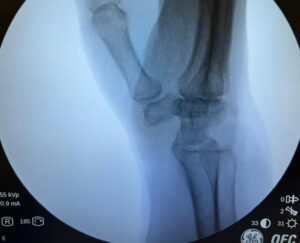

O procedimento realizado abaixo, em um paciente com Doença de Kienbock, é o(a):

CProcedimento de Illarramendi